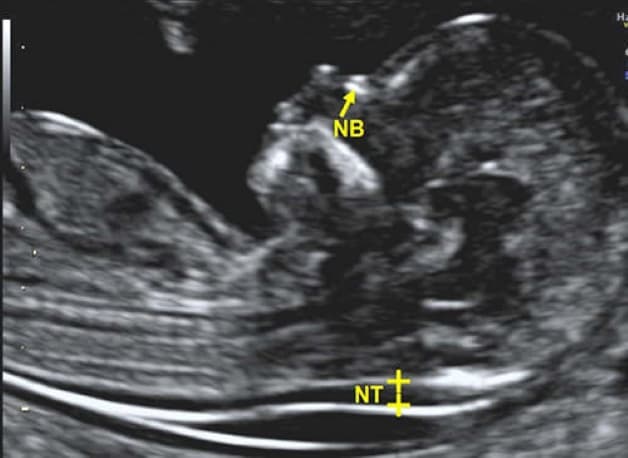

Siêu âm nhằm kiểm tra độ mờ da gáy là phương pháp tốt nhất giúp phát hiện sớm các bệnh do nhiễm sắc thể gây nên, điển hình là hội chứng Down. Vì vậy, loại kiểm tra này hiện đang được sử dụng rất nhiều ở các bệnh viện cũng như phòng khám.

Từ kết quả siêu âm sàng lọc tuần 12 thu được, nếu như độ mờ da gáy lớn hơn 3mm thì yêu cầu người mẹ cần tiến hành thêm xét nghiệm nước ối. Khi mà thai nhi mắc phải hội chứng Down thì tuyến nước bọt sẽ bị tắc, dịch ứ đọng lại và làm cho lớp da gáy dày hơn so với bình thường. Khoảng mờ da gáy bình thường là từ 1-1,5 mm. Khi càng dày hơn 3mm thì khả năng bị dị tật càng cao và cần phải tiến hành chi tiết hơn để giúp bác sĩ đưa ra được kết luận chính xác nhất.

Dựa vào siêu âm bác sĩ sẽ đo được độ mờ da gáy của thai nhi